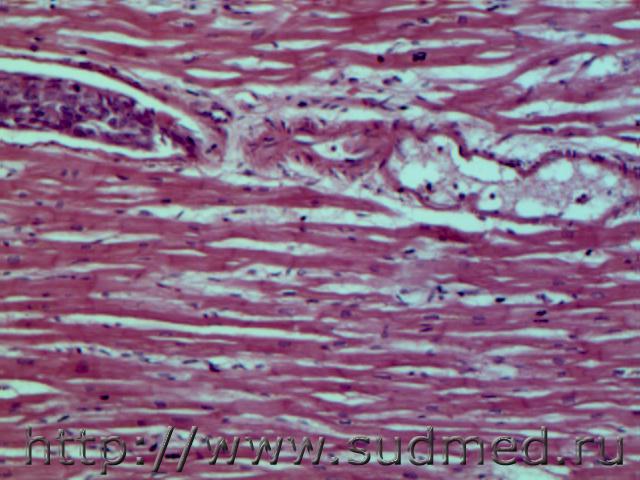

ВПС.ДМЖП. Диффузный интерстициальный миокардит(панкардит)( повреждение миоцитов с вакуолизацией субэндокардиально .Мальчик 5месяцев.